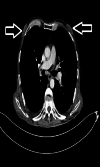

Background and objective Gynecomastia is a benign proliferation of ductal epithelium in the retroareolar region in male patients. The aim of this study was to investigate the frequency of gynecomastia in male patients who underwent thoracic computed tomography (CT) imaging at our clinic, assess possible causes, highlight the imaging characteristics of gynecomastia, and compare our findings with the literature. Materials and methods Male patients over 18 years of age who underwent thoracic CT imaging in our clinic were included in the study. Patients were initially assessed based on age and the presence of gynecomastia. The patients with gynecomastia were evaluated in terms of age, gynecomastia localization (right, left, and bilateral), gynecomastia type (nodular, dentritic, and diffuse), and possible etiology. Results The study included 1500 patients with a mean age of 45.6±21.7 years, and 470 (31.3%) patients had gynecomastia. Gynecomastia was on the right side in 11.3%, on the left side in 11.1%, and bilateral in 77.7% of the patients. Gynecomastia was nodular in 52.1%, dendritic in 35.3%, and diffuse in 17.2% of the patients. The causative factor could not be identified in 44.3% of the patients with gynecomastia. Among cases where the etiology was identified (56.7%), the most common factors were cancer (23.4%), chronic kidney disease (CKD) (13.2%), and chronic hepatitis B (10.7%). Conclusion When evaluating thoracic CT, the breast area, in addition to the lungs, chest wall, and bone structures, should also be evaluated carefully. With the increased use of thoracic CT scans, incidentally detected gynecomastia in patients is also on the rise. Knowing the presence of gynecomastia is very important for the clinician to determine the etiology and treat the underlying disease. Therefore, detecting and reporting gynecomastia on thoracic CT can prevent unnecessary advanced breast imaging methods and play a very important role in treating the underlying etiology.